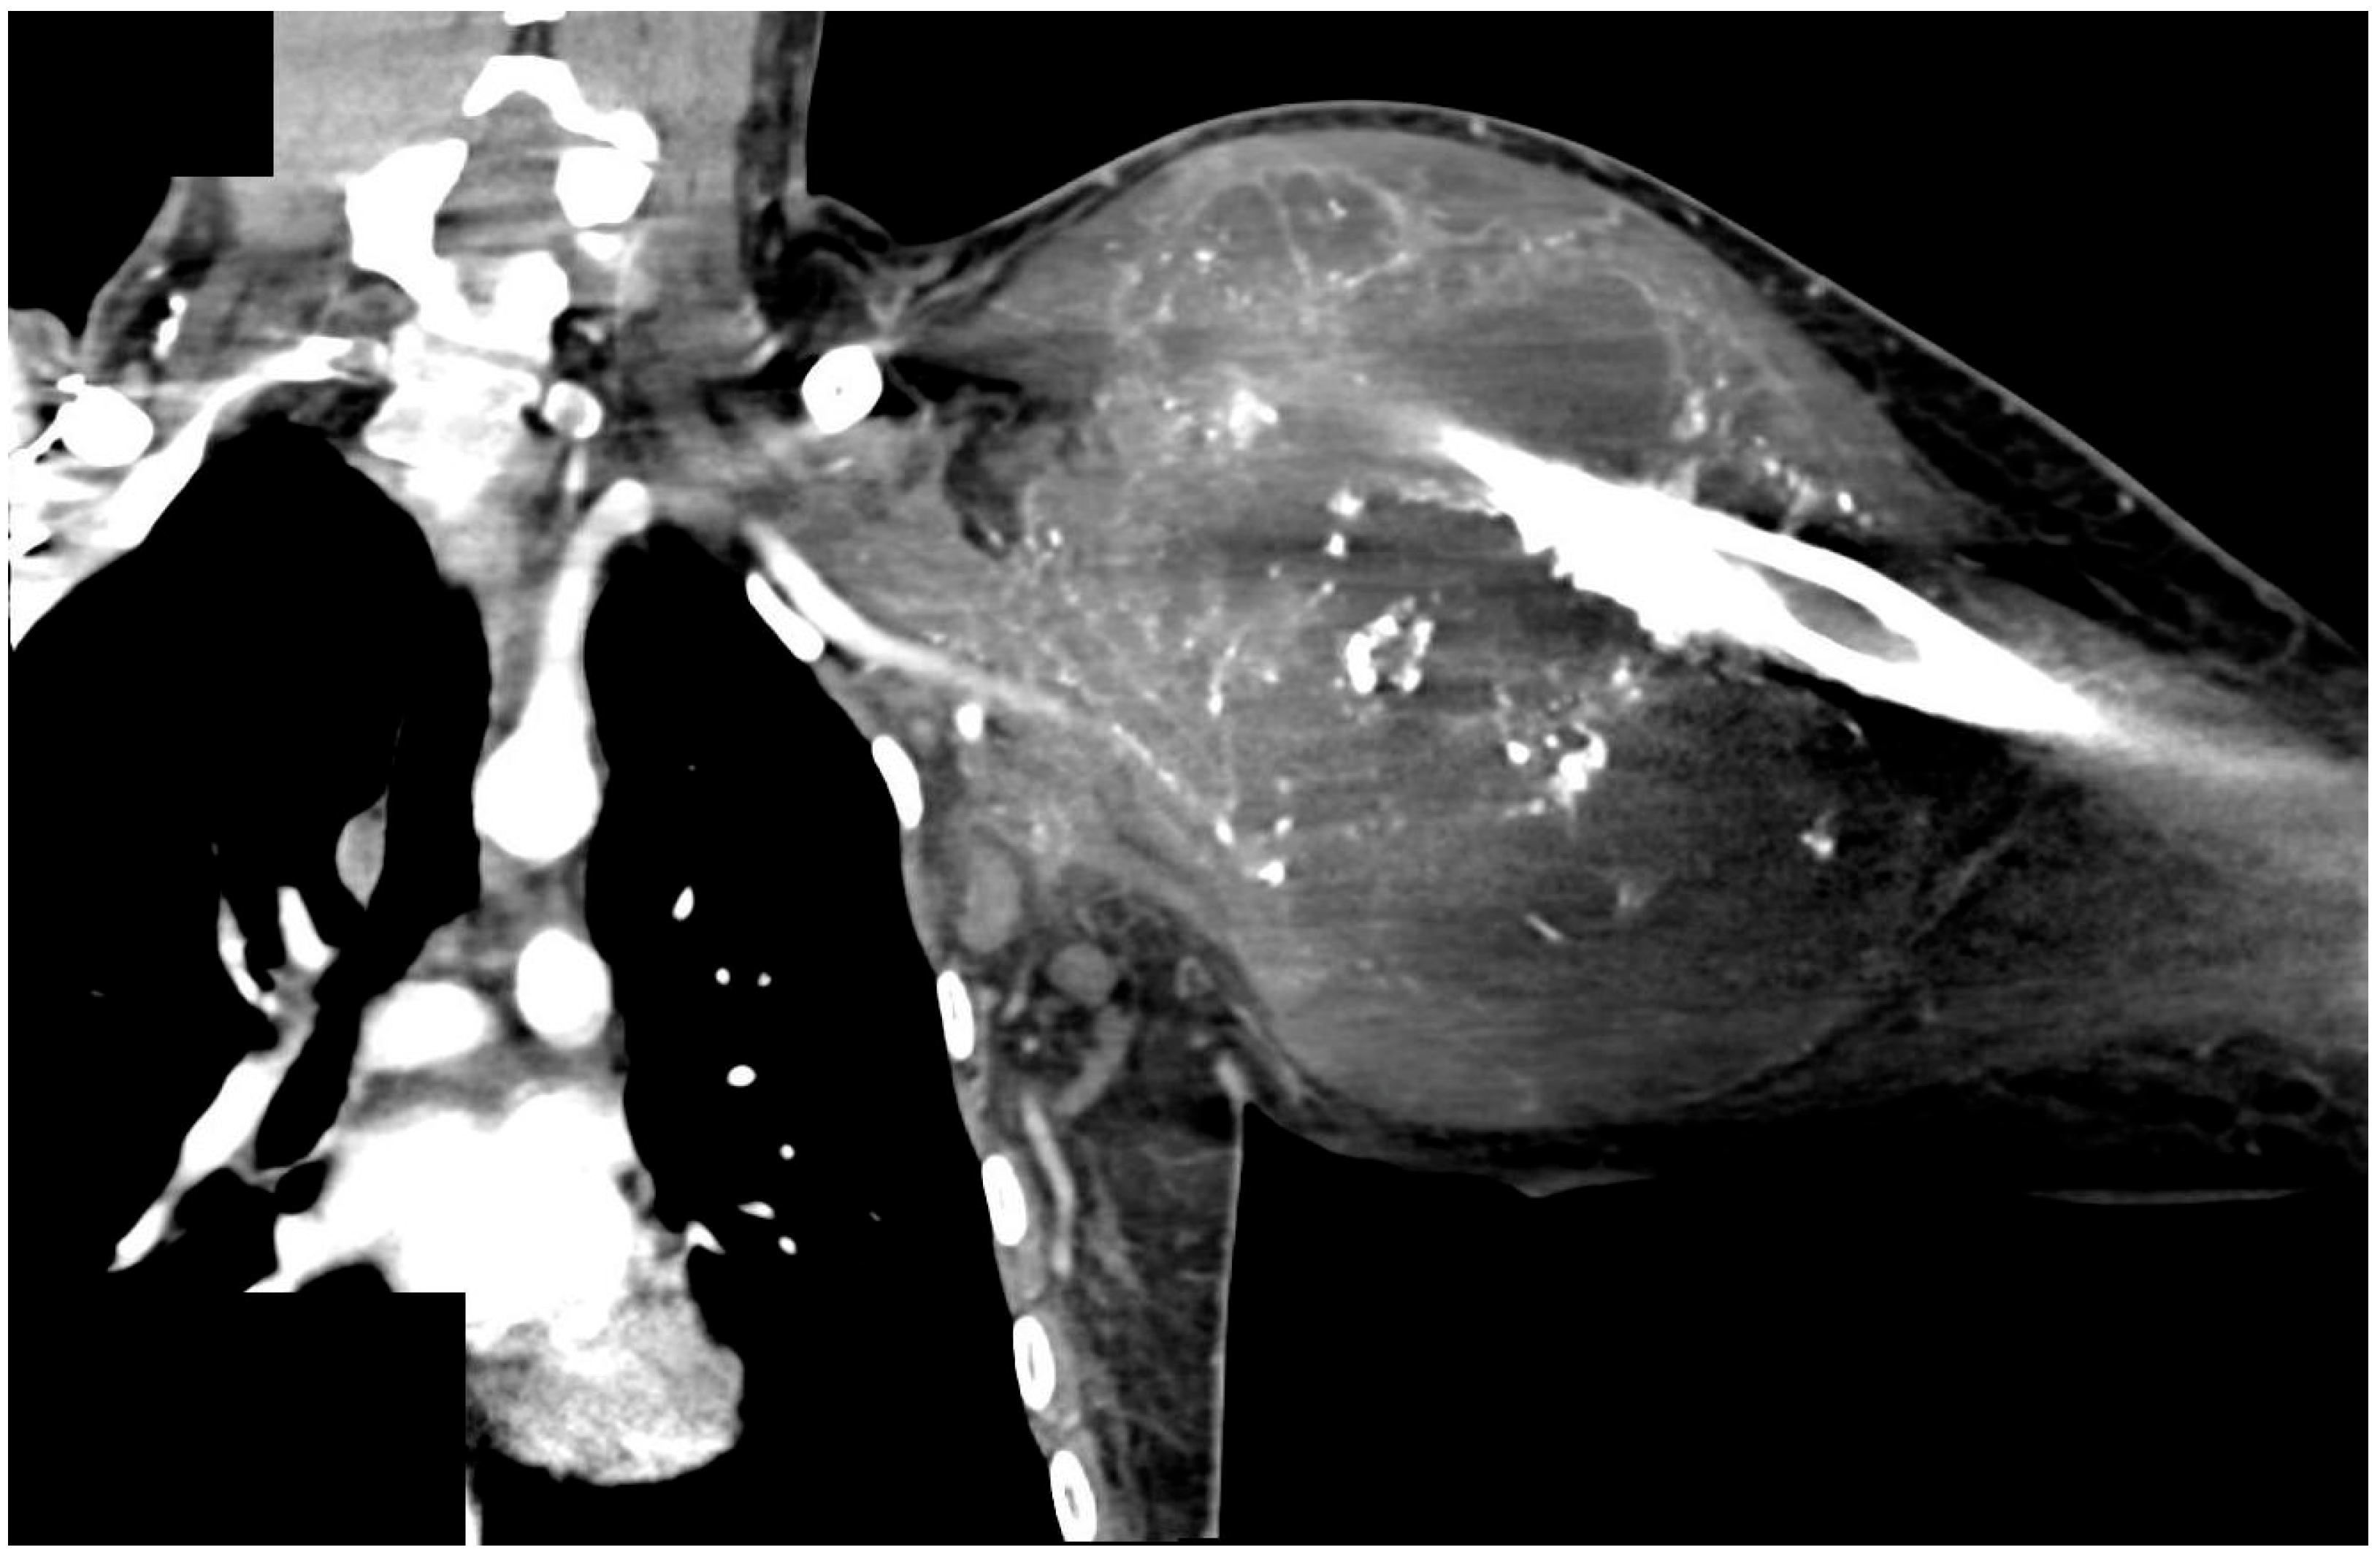

| 25 year old male with central chondroblastic osteosarcoma (cT2 cN0, cM1), extended FQA, including resection of the clavicle and the first three ribs | Brachial artery to thoracoacromial artery and cephalic vein to subclavian vein | Plate osteosynthesis between radius and sternum, 90° flexed wrist and fixation sutures between metacarpals and the lateral thoracic wall | Nerve coaptation between superior trunk and median nerve, middle trunk and radial nerve, and inferior trunk and ulnar nerve | Discharged after 11 days, stable osseous framework, Exitus letalis three months after surgery due to disseminated, primarily pulmonal, metastases |